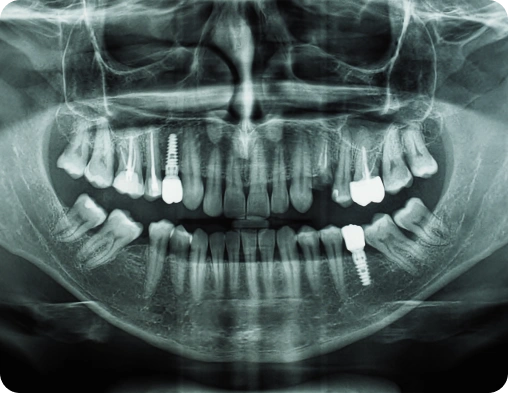

Speak with our team, ask questions, and schedule a full exam with 3D imaging to confirm candidacy.

Real Patients. Real Results.

Explore examples of smiles transformed at District Dental Solutions. Every case is unique—your treatment plan is customized after a full exam.

All transformations shown are real patients treated at our clinic. Individual results vary.